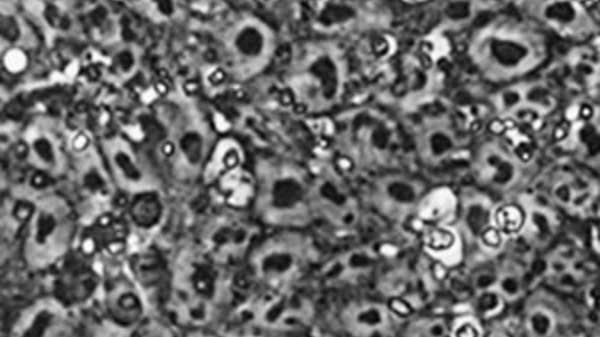

31+ Why Is Stem Cell Research Controversial UK. Ethical issues historically, the use of stem cells in medical research has been controversial. However, human embryonic stem cell details:

Stem cell research policy varies significantly throughout the world. Some government policies determine what is allowed versus prohibited, whereas others outline what research can be publicly financed. Stem cells represent an exciting area in medicine because of their potential to regenerate and repair damaged tissue. Do you have any interest in making ivf illegal?